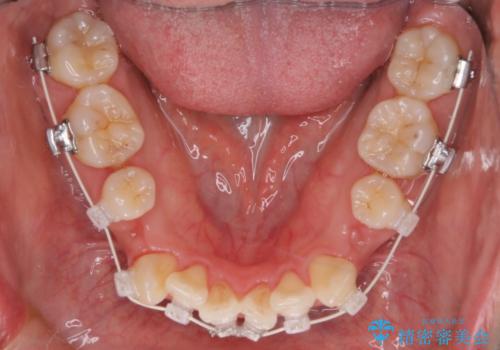

【審美装置】前歯のデコボコを綺麗に

- 上の前歯のデコボコが気になるということで来院されました。

叢生量(デコボコ)が多いため、上下左右4番目の歯を抜歯してワイヤー矯正を行う治療計画を立てました。

主訴である前歯のデコボコが改善され、噛みあわせも綺麗になりました。

歯肉退縮もなく、予定通りに治療を終えることができ良かったです。